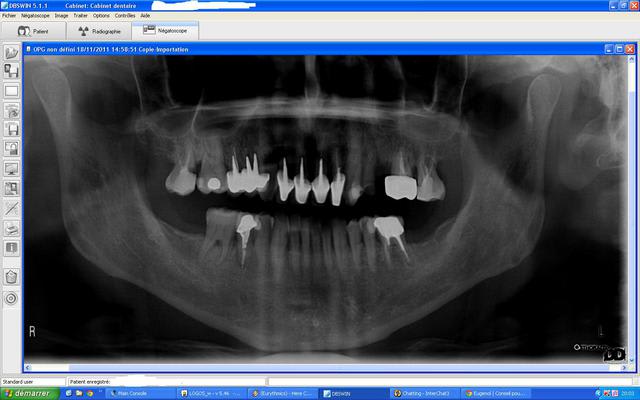

voilà la pano avec le meilleur traitement d'image que j'ai pu faire pour apercevoir quelque chose en apex de 45

PS= si quelqu'un veut m'expliquer comment faire des images jointes plus grosses ou de meilleures qualités envoyez moi la marche à suivre par MP pour éviter de pourrir ce post, merci